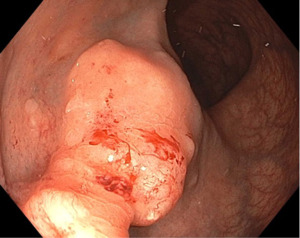

EGD and colonoscopy were performed to evaluate for a GI primary. EGD revealed no abnormalities in the esophagus, stomach, or duodenum. Colonoscopy identified a large rectal lesion resembling a submucosal tumor with a friable surface (Figure 5).